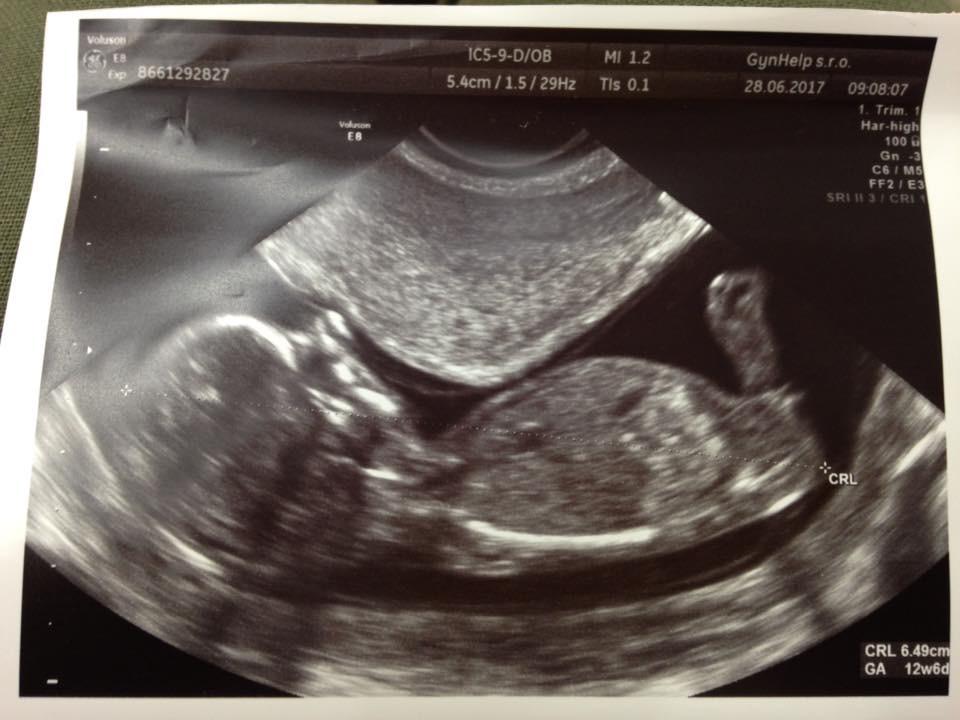

Myslím že holka dle pohlavního hrbolku ;)

Ja bych tipla chlapecka

Typuju holčičku :D je to podobné mému ultrazvuku a my holčičku čekáme :D Ale nikdy nevíš :p